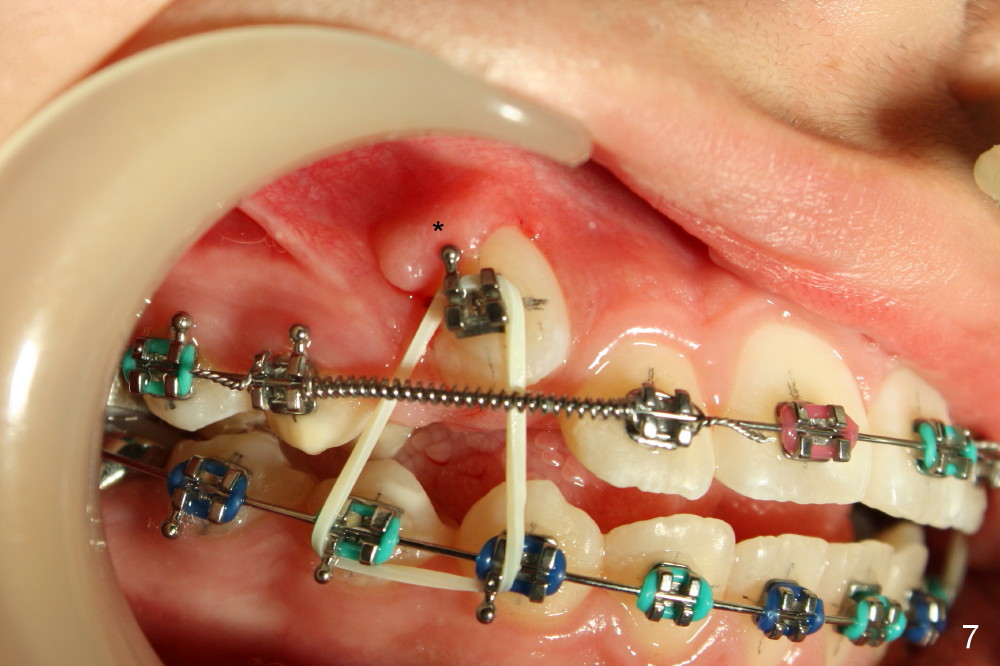

Eight days postop, the apical repositioning flaps have healed (Fig.7,8 *). The patient feels that U3s have been erupting more.